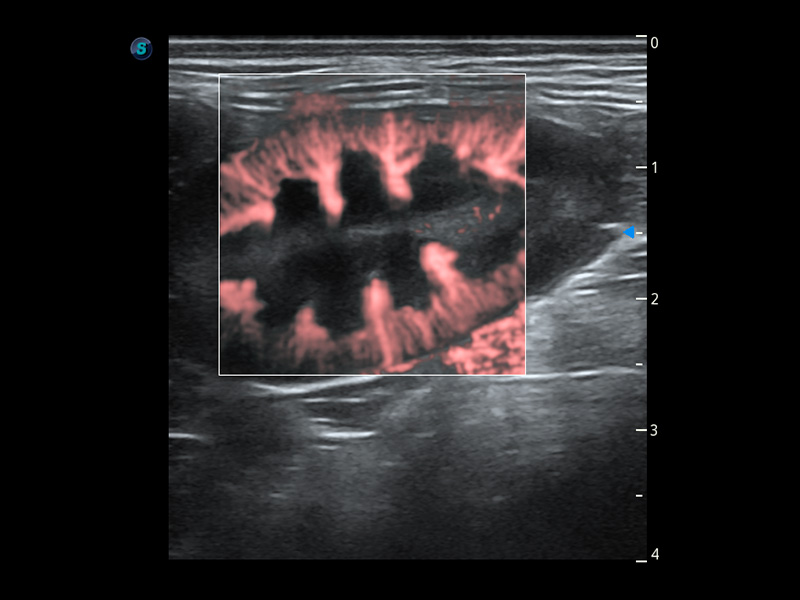

ProPet 60 作為一款高端臺(tái)式動(dòng)物超聲設(shè)備,為動(dòng)物醫(yī)生的日常診斷提供了一系列貼合動(dòng)物臨床需求、解決臨床實(shí)際問題的高級(jí)成像功能。憑借全系列高清探頭,滿足醫(yī)生對(duì)腹部、心臟、生殖、淺表、肌骨等成像的所有需求,切實(shí)幫助您提升檢查效率,提高診斷信心。